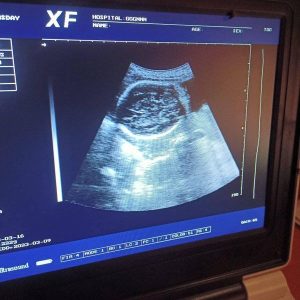

हुम्ला जिल्लाका ग्रामिण भेग सम्मै स्वास्थ्य क्षेत्रमा पहुच वढ्दै गएको छ । जिल्ला अस्पतालबाट मात्रै सेवा प्रवाह हुने हुम्ला जिल्लामा अहिले हुम्लाका ग्रामिण भेगबाटै सेवा प्रवाह हुन थालेका छन । यस अघि गर्भवति महिलाको गर्भमा रहेको शिसुको स्वास्थ्य अवस्था र आमाको शारीरिक अवस्था कस्तो छ भन्ने बारेमा जानकारी लिनका लागी जिल्लाका ७ वटै गाउँपालिकाका स्वास्थ्य संस्थाबाट सेवा प्रवाह हुन थालेका छन । स्वास्थ्य विभागको आर्थिक सहयोग सँगै गाउँपालिकाको पहलमा गर्भवति महिलाको भिडियो एक्सरेका लागी चाहिने आवश्यक स्वास्थ्य सामाग्री उपलब्ध भए पछि गाउँपालिकाकै स्वास्थ्य संस्थाबाटै गर्भवति महिलाको गर्भ चेक जाँच हुने गरेको छ ।

हुम्ला जिल्लाको मध्य क्षेत्रमा रहेको चंखेली गाउँपालिका वडा नं ४ मा रहेको पिप्लाङ बर्थिङ सेन्टरमा गर्भवति महिलाहरुका लागी भिडियो एक्सरे सुरु भएको स्वास्थ्यकर्मी वल कुमार शाहीले बताएका छन् । सो वर्थिङ सेन्टरमा गर्भवति महिलाको भिडियो एक्सरे सुरु भए पछि सोही गाउँपालिका वडा नं ४ का गर्भवति महिला सँगै अन्य वडाका महिलाहरु पनि गर्भ चेक जाँच गर्न सोही वर्थिङ सेन्टरमा आउने गरेको शाहीले बताएका छन् । गर्भ अबस्थामा कम्तीमा ३ पटक र अन्य समस्या परेमा जतिखेर पनि video x-ray सेवा लिदा आमा र गर्भमा रहेको शिशुको समस्या समयमा पत्ता लाग्ने भएकाले चंखेली गाउँपालिकाको सहकार्यमा सो वर्थिङ सेन्टरमा भिडियो एक्सरे सेवा सुरु गरिएको जानकारी प्राप्त भएको छ । गर्भमा रहेको बच्चाको अवस्था केछ उल्टो सुल्टो के छ पोष्ण पुगेको छ वा छैन लगाएतका स्वास्थ्य सम्बन्धी जानकारी लिनका लागी पनि भिडियो एक्सरे सेवा संचालन भएको खवर प्राप्त भएको छ ।